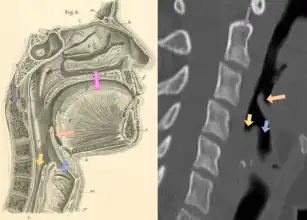

| Neck X-ray showing thumbprint sign. | |

Epiglottitis was historically mostly caused by infection by H. influenzae type b (commonly referred to as "Hib").[1] With vaccination, it is now more often caused by other bacteria, most commonly Streptococcus pneumoniae, Streptococcus pyogenes, or Staphylococcus aureus.[1] Predisposing factors include burns and trauma to the area.[1] The most accurate way to make the diagnosis is to look directly at the epiglottis.[3] X-rays of the neck from the side may show a "thumbprint sign" but the lack of this sign does not mean the condition is absent.[1]

On lateral C-spine X-ray, the thumbprint sign describes a swollen, enlarged epiglottis.[10] A normal X-ray, however, does not exclude the diagnosis.[10] An ultrasound may be helpful if specific changes are present, but its use (as of 2018) is in the early stages of study.[10]

On CT imaging, the "Halloween sign" describes an epiglottis of normal thickness. It can safely exclude the acute epiglottitis. Furthermore, CT imaging can help to diagnose other conditions such as peritonsillar abscess or retropharyngeal abscess which have similar clinical features.[21]